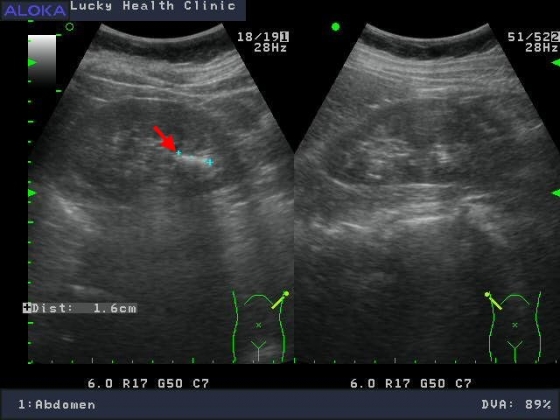

膽結石

腎結石